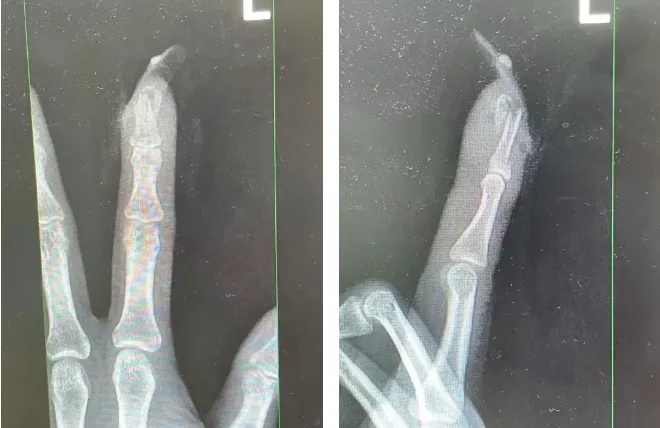

王女士受伤手指的X光影像。图源:杭州市临平区中西医结合医院

经检查

王女士指甲断裂

部分甲床外露

医生表示如果没有美甲

伤害不会这么严重